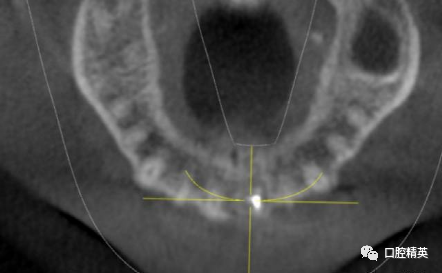

术后CBCT

术后两周拆线,复查X光片。

美学区软组织无退缩或外形改变。根尖区充填密实,根尖周组织初步愈合。记录牙体颜色变化。交代注意事项,4-6周复查。3-6个月完成美白及修复治疗。